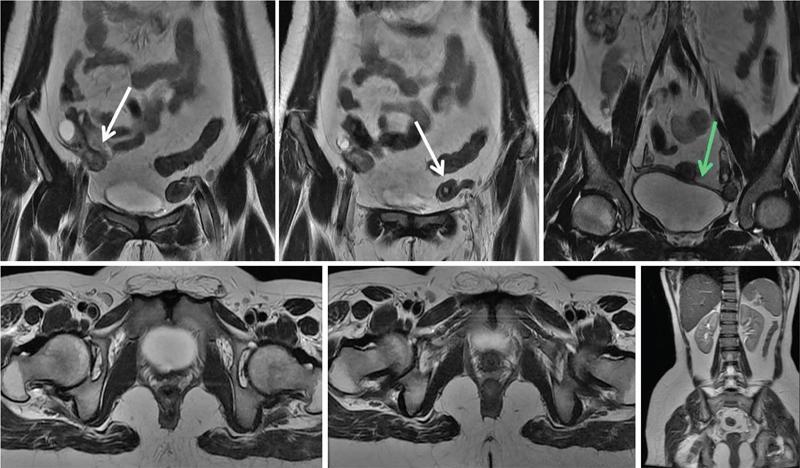

MÜLLERIAN DUCT ANOMALIES Rajani Gorantla Müllerian ducts are a pair of tubular structures that give rise to uterus, cervix, fallopian tubes and upper two-thirds of vagina. Disruption or failure of normal development can result in occurrence of Müllerian duct anomalies (MDAs). These are commonly associated with other congenital anomalies of urinary tract and ovaries due to the close relationship between the development of mesonephric and paramesonephric ducts; few patients also have associated skeletal system anomalies. The prevalence of MDAs in an unselected population was 5.5%; 8% among the infertile women, 12.3% in women with a history of recurrent pregnancy loss and 24.5% in women with miscarriage and infertility. Most of the patients with MDAs are asymptomatic and found incidentally on imaging for any other gynaecological problems, in evaluation of a patient with renal, skeletal or abdominal wall abnormalities. In symptomatic women, complains are related to the type, severity, obstructive anomaly or nonobstructive anomaly. The symptoms can be obstetric or gynaecological related, includes recurrent spontaneous abortions, infertility, preterm labour, intrauterine growth restriction and abnormal foetal lie. Few adolescent girls may present with primary amenorrhoea, hypomenorrhoea, abnormal vaginal bleeding, cyclical pain and mass. Rarely they can present with pelvic inflammatory disease with abnormal vaginal discharge, dyspareunia and urinary tract infections. The female reproductive system develops from a pair of Müllerian or paramesonephric ducts, urogenital sinus and vaginal plate. The ovaries develop separately from the primordial ridge. It is of great importance to understand the normal stages of development, as failure or interruption of any of these stages can lead to a simple to complex spectrum of anomalies. The three stages of Müllerian duct development include: At 6–10 weeks of gestation age, two paired Müllerian ducts and Wolffian ducts formation occurs. When Y chromosome factor (testicular determining factor) is absent, the Wolffian ducts undergo degeneration. The Müllerian ducts further elongate caudally and cross the Wolffian ducts to fuse in the midline. At 10–13 weeks of gestation age, caudal and lateral fusion of the two Müllerian ducts forms primitive uterovaginal canal, which is possessed of solid tissue initially located side by side and further internal canalization leads to the formation of two channels/canals divided by a septum. At this stage, there is reabsorption of the caudal septum and forms single cervical canal and vagina lumen. In around 15–20 weeks of gestation age, complete resorption of the septum takes place in a caudocranial direction from the isthmus to fundus and development of single endometrial cavity results. The fused caudal part of Müllerian ducts gives rise to the uterus, cervix and upper two-thirds of vagina; the unfused cranial part forms the fallopian tubes (Fig. 11.14.1.1). The lower vagina develops from the urogenital sinus, which is separated from the rectum by urorectal septum around 7 weeks of gestation age. The primitive uterovaginal canal embeds into the dorsal wall of urogenital sinus and forms Muller’s tubercle. Around 13 weeks of gestation, two solid masses known as sinovaginal bulbs originate from the upper part of the Muller’s tubercle, further proliferate into the caudal end of the uterovaginal canal to become a solid vaginal plate. Later canalization or degeneration of the central cells of the vaginal plate forms the lower vagina, which is usually completed by 20 weeks’ gestation. The vertical fusion of the upper and lower vagina occurs with resorption of tissue in between and forms single vaginal cavity (Fig. 11.14.1.2). The vaginal lumen is separated from the urogenital sinus by the hymenal membrane. Just before birth, the hymen normally ruptures due to retrogression of the central epithelial cells. However, a thin fold of mucous membrane persists around the vaginal introitus. The ovaries develop separately from migration of primordial germ cells to the genital ridge. Ureteric buds develop separately and concurrently. So renal anomalies are most commonly associated with MDAs with an association of 30%–50%. Various classification systems have been proposed over the past several decades to describe MDAs. Ideally, same classification system needs to be followed by a gynaecologist, surgeon and radiologist for better communication. Buttram and Gibbons classification was suggested in 1979, and it was based upon the level of failure in normal development and segregate the anomalies into groups with similar clinical manifestations, treatment, and prognosis for foetal salvage. According to Buttram and Gibbons, the uterine anomalies were classified into six classes as described in Table 11.14.1.1. The drawback is the lack of classification of vaginal and other anomalies separately. The ASRM (previously the American Fertility Society – AFS) classification system is the most widely accepted classification worldwide over the past years and was introduced in 1988. According to this classification, MDAs are classified into seven classes (class I to class VII) as mentioned in Table 11.14.1.2. However, several limitations have been described by Grimbizis and Campo in 2010 (Fig. 11.14.1.3). The drawbacks of the ASRM classification system are as follows: Hence in 2016, an updated classification of uterine septum, that is ASRM-2016 was proposed and officially approved morphometric criteria are given for distinguishing between septate, normal/arcuate and bicornuate uteri (Table 11.14.1.3). The VCUAM classification was proposed in the year 2005. The main concern is to provide a simple, systematic, clinical classification in addition to providing a precise reflection of the entire malformation. The female genital organs were divided into the following subgroups in accordance with the anatomy: vagina (V), cervix (C), uterus (U) and adnexa (A). Associated malformations were assigned to a subgroup (M) relative to each specific organ. The disadvantage is due to its inherent complexity, and more than 56,700 individual combinations of anomalies are possible. ESHRE and ESGE established a common working group named CONgenital UTerine Anomalies (CONUTA) in order to devise an improved classification system (Table 11.14.1.4). It was published in 2013. Anatomy is the basis for systemic categorization of the MDAs. The subclasses are divided by the different degrees of uterine deformity and their clinical significance (Fig. 11.14.1.4). Cervical and vaginal anomalies are classified into independent supplementary subclasses (Figs. 11.14.1.5–11.14.1.6). For most of the clinicians, it helped as starting point for the development of guidelines for their diagnosis and treatment. The malformations are graded according to severity, U0–U5, C0–C4 and V0–V4, with U5, C4 and V4 being more severe. Class U3 incorporates bicorporeal fusion defects (didelphys and bicornuate) as this was considered as a more functional mode of classification. Arcuate uterus was not included separately, but this is categorized under normal variant into class U1c. Recent studies have demonstrated that the ESHRE/ESGE system provides an effective and comprehensive classification for almost all the currently known MDAs and overcomes the limits of previous classifications. However, there is a relative overdiagnosis of septate uterus with the application of ESHRE–ESGE criteria has been reported and which potentially might lead to unnecessary surgical overtreatment. C0 C1 C2 Normal cervix Septate cervix Double ‘normal’ cervix C3 C4 Unilateral cervical aplasia Cervical aplasia U4 V0 V1 V2 V3 Normal vagina Longitudinal nonobstructing vaginal septum Longitudinal obstructing vaginal septum Transverse vaginal septum and/or imperforate hymen V4 Vaginal aplasia C MDAs’ characterization and classification is of great significance, as the treatment is determined by the type and severity of abnormality. The various imaging modalities available include: HSG was the most recognized imaging modality, earlier to the development of the ultrasonography (USG) and MRI. It is an invasive fluoroscopic-guided procedure for uterine and tubal assessment, and is performed during the midproliferative phase of the cycle, ideally between days 7 and 10 of the cycle when endometrium is thin. Fluoroscopic spot images obtained to evaluate uterine configuration, uterine filling defects and fallopian tube patency. HSG allows evaluation of only the component of the uterine cavity that communicates with the cervix. The anatomic information about myometrium and external fundal contour will not be provided by HSG. The diagnostic criteria used to diagnose MDAs on HSG include: HSG findings of different MDAs are described in Table 11.14.1.5 and Fig. 11.14.1.10. Virtual HSG is a noninvasive technique performed by using a computed tomography (CT) scanner, done 45 s after the contrast material instillation begins. Contraindications are similar to those for HSG and include pregnancy and active pelvic infection. There is no necessity for retraction of the uterus or manipulation of the cervix. The procedure is quick, easy and prophylactic administration of antibiotics is not required. The use of a power injector helps to ensure a steady low pressure of instillation. The procedure is less painful, more comfortable and easily tolerated by patients than conventional HSG. Radiation exposure sometimes requires cervical clamping, which may result in complications such as bleeding and infection. Transabdominal pelvic ultrasound can diagnose uterine anomalies with accuracy rate of 47%. Two-dimensional transvaginal ultrasound (TVUS) has high sensitivity and specificity than transabdominal study and provided some information about external and internal fundal contours. The detection rate is high if the scan is performed in secretory phase due to better visualization of endometrium. Three-dimensional USG shows great accuracy than 2D USG in evaluation of the uterine morphology. The technique of 3D USG varies with different vendors. It displays both the external and internal fundal contours and lower uterine segment by acquisition of single coronal view of uterus (c-view) (Fig. 11.14.1.11). The only disadvantage is that it is transvaginal study and shall not be done in paediatric age group and sexually inactive women. Three-dimensional TVUS has become the first line of screening tool in most of the infertility clinics as it is noninvasive, faster, repeatable, allows storage of volume data and has multiplanar capability for systematic evaluation of the uterine and cervical cavities. The salient features of various Müllerian anomalies on 3D USG are described in Table 11.14.1.6 with images. Three-dimensional ultrasound is combined with sonosalpingography in this technique and provides better delineation of the uterine morphology. It is a less invasive procedure done in proliferative phase with instillation of saline into the uterine cavity and assessment of the uterus will be done. MRI is a universally accepted imaging modality in the documentation of MDAs and accuracy rate of 100% have been reported. MRI provides excellent delineation of both the internal and external uterine anatomies. T2-weighted (T2W) images are the mainstay of pelvic imaging and are performed without fat suppression. T1-weighted (T1W) images are mainly for the haemorrhagic content. The disadvantages of MRI include time-consuming procedure, not cost-effective, large body habitus, pacemakers, recent surgical history and claustrophobia. The current and proposed MRI protocol given by the European Society of Urology (ESUR-MRI protocol) intends a dedicated evaluation of MDAs as mentioned below (Fig. 11.14.1.12): Vaginal anomalies can be accurately diagnosed with the prior administration of the ultrasound gel, to distend vagina (Fig. 11.14.1.13). It will help in better diagnosis of complex vaginal anomalies, like vaginal septations or vaginal duplication. The normal MRI appearance of uterocervical canal and vagina are shown in Fig. 11.14.1.14. Uterine aplasia/hypoplasia/agenesis is class 1 MDA according to ASRM classification and U5 uterine anomaly according to ESHRE classification. It is a formation defect of the paramesonephric ducts with complete or segmental agenesis of uterus and vagina. The incidence rate is around 10%–15% of all MDAs and considered as the most severe form of uterine anomaly. Most of them have complete uterovaginal agenesis with no single completely developed uterine cavity and are associated with Mayer–Rokitansky–Küster–Hauser syndrome (MRKHS). Two types of this syndrome are depicted. The typical form or type A represents the absence or remnants of the uterus, cervix, upper two-thirds of vagina with normal ovaries and fallopian tube (Fig. 11.14.1.15). The atypical form or type B is associated with the abnormalities of the ovaries, fallopian tubes and genitourinary system (Fig. 11.14.1.16). In a few cases (approximately 10%), unilateral or bilateral uterine remnants and with or without endometrial cavity will be seen (Fig. 11.14.1.17). Most of them present with primary amenorrhoea due to complete uterovaginal agenesis and manifest as MRKHS. These patients have normal secondary sexual characteristics due to the preserved normal ovarian function and phenotype. If uterine remnants with functional cavity is present, will present with cyclical pain along with amenorrhoea due to cryptomenorrhoea and haematometra. USG is the first modality for identification of these anomalies, absence of uterus with normal ovaries is diagnostic. But, it is difficult to locate the uterine remnants and cavity due to small acoustic window. MRI is the gold standard and it classifies into uterovaginal agenesis and hypoplasia. If hypoplasia is identified, sagittal and axial sections are taken. These remnants are seen as T2 hypointense tubular structures, located in close relation to ovaries in the adnexa. Once we identify the uterine remnants, it is important to look for the functional endometrial cavity. These will have reduced endometrial and myometrial width. MRI can easily delineate the zonal anatomy due to its high soft tissue contrast resolution. The management of Müllerian agenesis consists of counselling for the patient and her parents. Some patients with MRKHS opt for creation of neovagina for normal sexual life. Various techniques are available. In the presence of a functional Müllerian remnant, regardless of whether it is communicating or not, medical suppression of menses can be initiated and should be followed by laparoscopic removal of the hypoplastic remnant. Unicornuate uterus or hemiuterus is defined as the unilateral uterine development and the contralateral Müllerian duct could be either partially formed or absent. It is a formation defect and the necessity to classify it in a different class than that of uterine agenesis, which is also a formation defect, is due to the existence of a fully developed functional uterine hemicavity. It is considered as class II anomaly according to ASRM classification and class U4 according to ESHRE classification. The frequency rate is around 20% of MDAs. Renal anomalies most often occur in association with unicornuate uterus and usually on the same side of uterine agenesis. Further unicornuate uterus is divided into two subclasses depending on the presence or absence of a functional rudimentary cavity in ESHRE classification: In ASRM classification, unicornuate uterus is divided into four subcategories: Mostly asymptomatic and presence of the noncommunicating uterine remnants will be identified at the time of infertility work up or caesarean section. If a functional cavity is present, the presentation is dysmenorrhoea or haematometra in an adolescent. The common obstetrics-related complications include abnormal foetal lie, intrauterine growth retardation, preterm delivery, placental abnormalities and uterine rupture. Gynaecological complications are ectopic pregnancy and endometriosis due to retrograde menstruation. On imaging, unicornuate uterus is seen as tubular and fusiform or banana-shaped structure at paramedian location, the endometrium is narrow and tapers to the apex with normal myometrial anatomy and reduced uterine volume. The rudimentary cavity or remnants are better depicted on 3D USG (Fig. 11.14.1.18) and MRI. However, MRI is superior to USG due to its high soft tissue resolution. The rudimentary cavity can communicate with main cavity or connected by fibrous band. The nonfunctioning cavity will be seen as T2 hypointense structure with loss of zonal anatomy (Figs 11.14.1.19 and 11.14.1.20), whereas the functioning cavity will show the deformed zonal anatomy (Fig. 11.14.1.21), and its complications like haematometra as T1/T2 hyperintense endometrial collection. Unicornuate uterus without rudimentary cavity does not require any procedure. But in the presence of communicating or noncommunicating rudimentary horn, surgical resection must be considered to prevent complications. Uterine didelphys is a class III MDA based on the ASRM classification and class U3b bicorporeal uterus according to ESHRE classification with an incidence rate of 5% among the uterine anomalies. It is a lateral fusion defect; results from complete failure of the Müllerian duct fusion. Two noncommunicating endometrial cavities with preserved zonal anatomy are seen with separate cervix. According to ESHRE classification, it is defined as external fundal indentation completely dividing the uterine corpus up to the level of external cervical os. It is most commonly associated with longitudinal vaginal septum in around 75% of cases. Some patients may show transverse vaginal septum and these will be obstructive or nonobstructive type. Renal anomalies are also commonly associated with uterine didelphys. Uterine didelphys is usually asymptomatic and diagnosed incidentally on pelvic examination or caesarean section. The uterine didelphys with obstructed vagina (Fig. 11.14.1.22) will present at adolescence as dysmenorrhoea, haematometrocolpos and haematosalpinx. Sometimes retrograde menstrual flow can cause endometriosis and pelvic adhesions. Obstetric-related complications include abortion/foetal growth restriction and poor pregnancy outcome. The uterine didelphys with obstructed hemivagina due to transverse vaginal septum and associated ipsilateral renal agenesis are the manifestations of the syndrome called obstructed hemivagina and ipsilateral renal agenesis anomaly/Herlyn–Werner–Wunderlich (HWW) syndrome (Fig. 11.14.1.23).